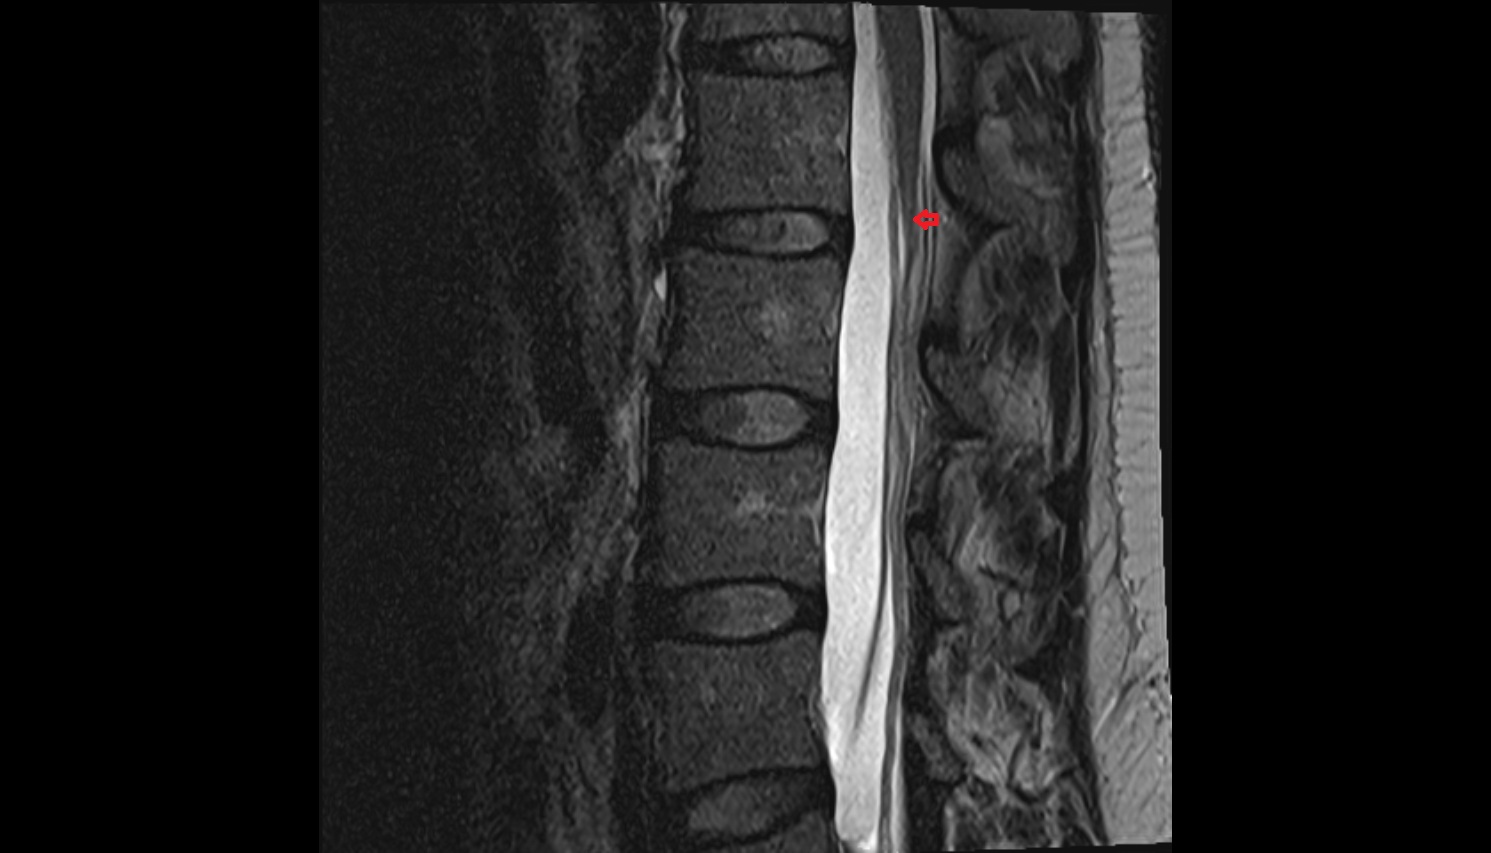

- Cauda equina

- Conus medullaris

- Filum terminale internum

- Spinal dura mater

- Spinal epidural space